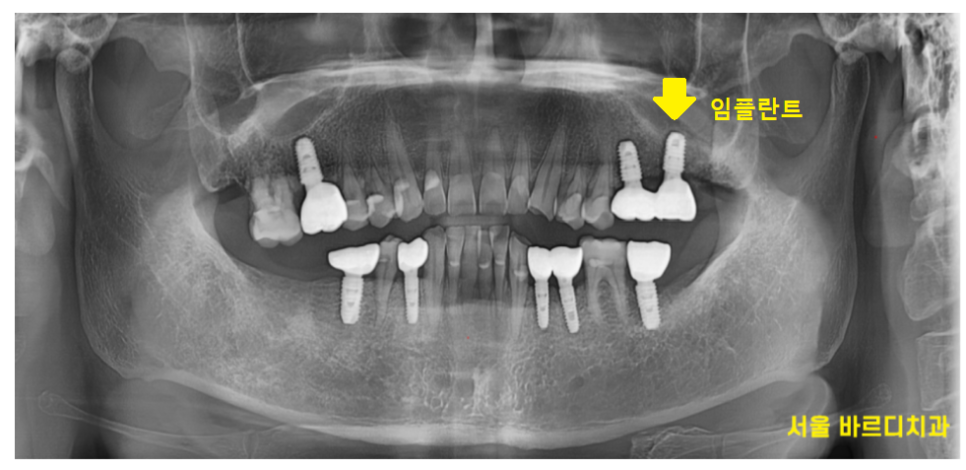

서울 바르디치과는

수술 후 임플란트 보증서를 드리는데

임플란트 스티커를 붙여드립니다.

회사, 사이즈 확인하실 수 있게요.

서울 임플란트 병원 중에서는

뼈이식을 안하고 했다고 하는 병원도 있다는데요

저희는 수술 과정도 자세하게 사진으로

기록하는 병원입니다.

사기치지 않습니다.

이 뽑은 사진

염증 제거한 사진

사용한 뼈

모두 찍어 보여드립니다.